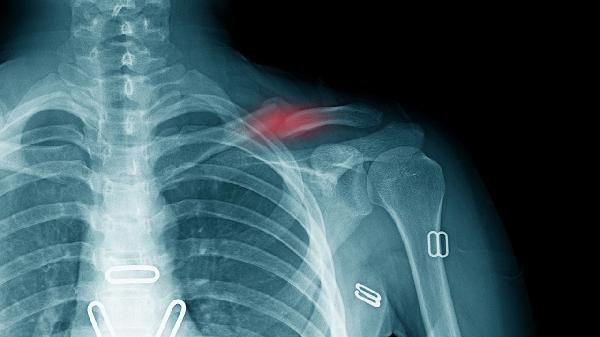

小脚趾骨折多数为轻微裂纹骨折或无移位骨折,这类情况通过外固定即可达到愈合目的。石膏固定能维持骨折端稳定,通常需持续4-6周。固定期间应避免患肢负重,定期复查X线观察愈合情况。疼痛明显时可遵医嘱使用布洛芬缓释胶囊、对乙酰氨基酚片等镇痛药物。

当骨折端成角超过30度、断端分离超过5毫米或伴有皮肤破损时,手术干预更为必要。克氏针内固定术能有效恢复解剖结构,术后需配合抗生素如头孢呋辛酯片预防感染。对于严重粉碎性骨折,可能需微型钢板螺钉系统固定,术后早期需进行足趾功能锻炼防止关节僵硬。